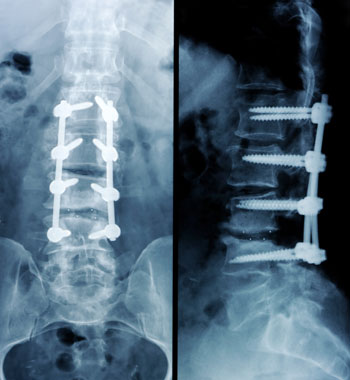

FDA Decides to Delay UDI Labeling Rule for Some Orthopedic Implants